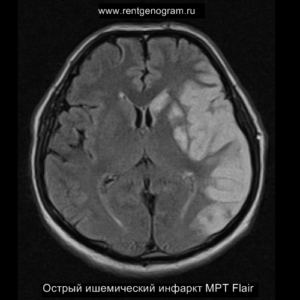

Острая фаза (6 — 24 часа)

В течение острого этапа на МРТ и КТ выявляются все морфологические признаки ишемического инсульта. Область острого ишемического инфаркта визуализируется как зона ↑Т2, ↑Flair, ↑DWI и ↓Т1 ↓ADC. Можно обнаружить тромб в артерии. На КТ в остром этапе также чётко дифференцируется поражённая область, представляющая собой участок с потерей дифференциации мозговых структур и снижением их плотности. Контрастирование в остром периоде не показывает патологических участков с накоплением контраста.